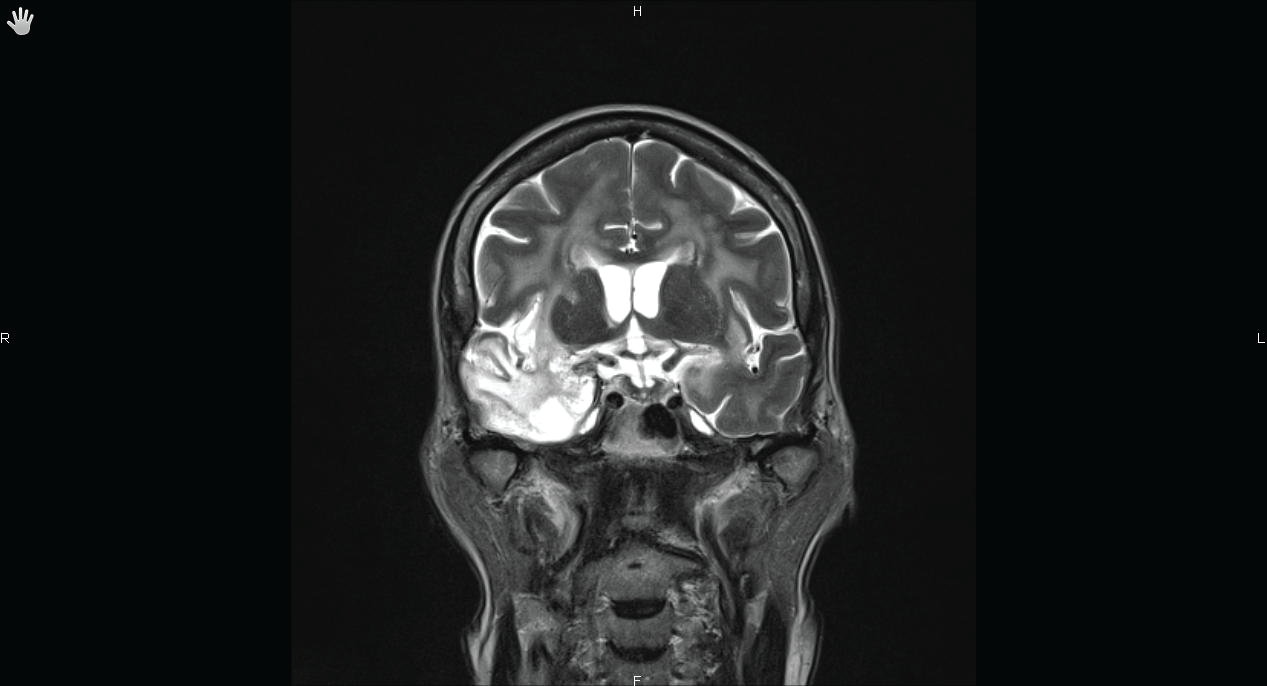

Unfortunately, the patient experienced refractory seizures requiring prolonged sedation and mechanical ventilation in the intensive care unit (ICU). The evolution was marked by the recovery of sinus node dysfunction allowing the discontinuation of isoprenalin, and disappearance of epileptic figures on electroencephalogram (EEG). After a 3-months follow-up, there was no sinus pause recurrence and a complete neurologic recovery was achieved. A cerebral Magnetic Resonance Imaging (MRI) performed seven months after the onset of the illness showed persistent signal abnormalities in the right temporal lobe and more particularly in the right insula (Figures 2A,2B).

Common symptoms of herpes simplex encephalitis include fever, headache, consciousness impairment, focal neurological signs, and seizures. Definite diagnosis is based on PCR detection of HSV DNA in the CSF, with a sensitivity of 98%, a specificity of 94%, a positive predictive value of 95% and a negative predictive value of 98% in adults [1,3,6]. In more than 90% of patients, MRI reveals temporal and/or inferior frontal lobe oedema with high signal intensity on FLAIR and T2-weighted images [1]. Recent data suggested temporal trends of brain involvement with a relative superiority of DWI sequences over FLAIR's ones to detect involved areas (especially cortical) in acute and subacute phase of HSV encephalitis except for thalamic attempt early identified by FLAIR imaging [7]. In the late phase of disease, FLAIR is superior, mainly to detect white matter involvement.

All these data highlight the fact that injury of insular cortex especially in its right side, that is thought to be involved in the control of autonomic system, can result in central sinus node dysfunction [20], whatever the aetiology [15]. Anterior cingulated cortex seems to play a major role in the central autonomic network [21], but to our knowledge, lesions of this area have not been proved to be associated with cardiac disturbance.